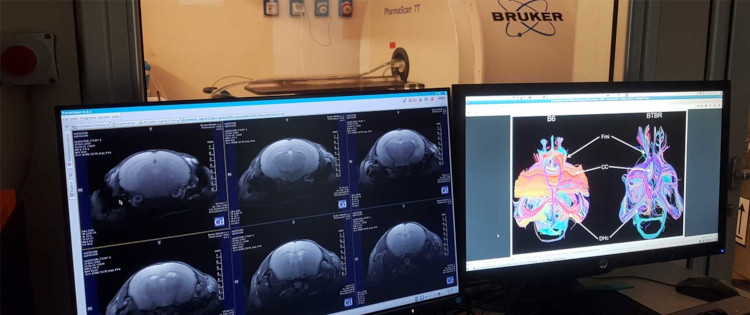

Center for Synaptic Neuroscience and Technology

Università di Genova, Genova

Il Center for Synaptic Neuroscience and Technology (NSYN) applica un approccio multidisciplinare allo studio delle funzioni cerebrali e alle patologie correlate. Lo scopo è sviluppare tecnologie innovative applicabili nell'ambito delle neuroscienze.